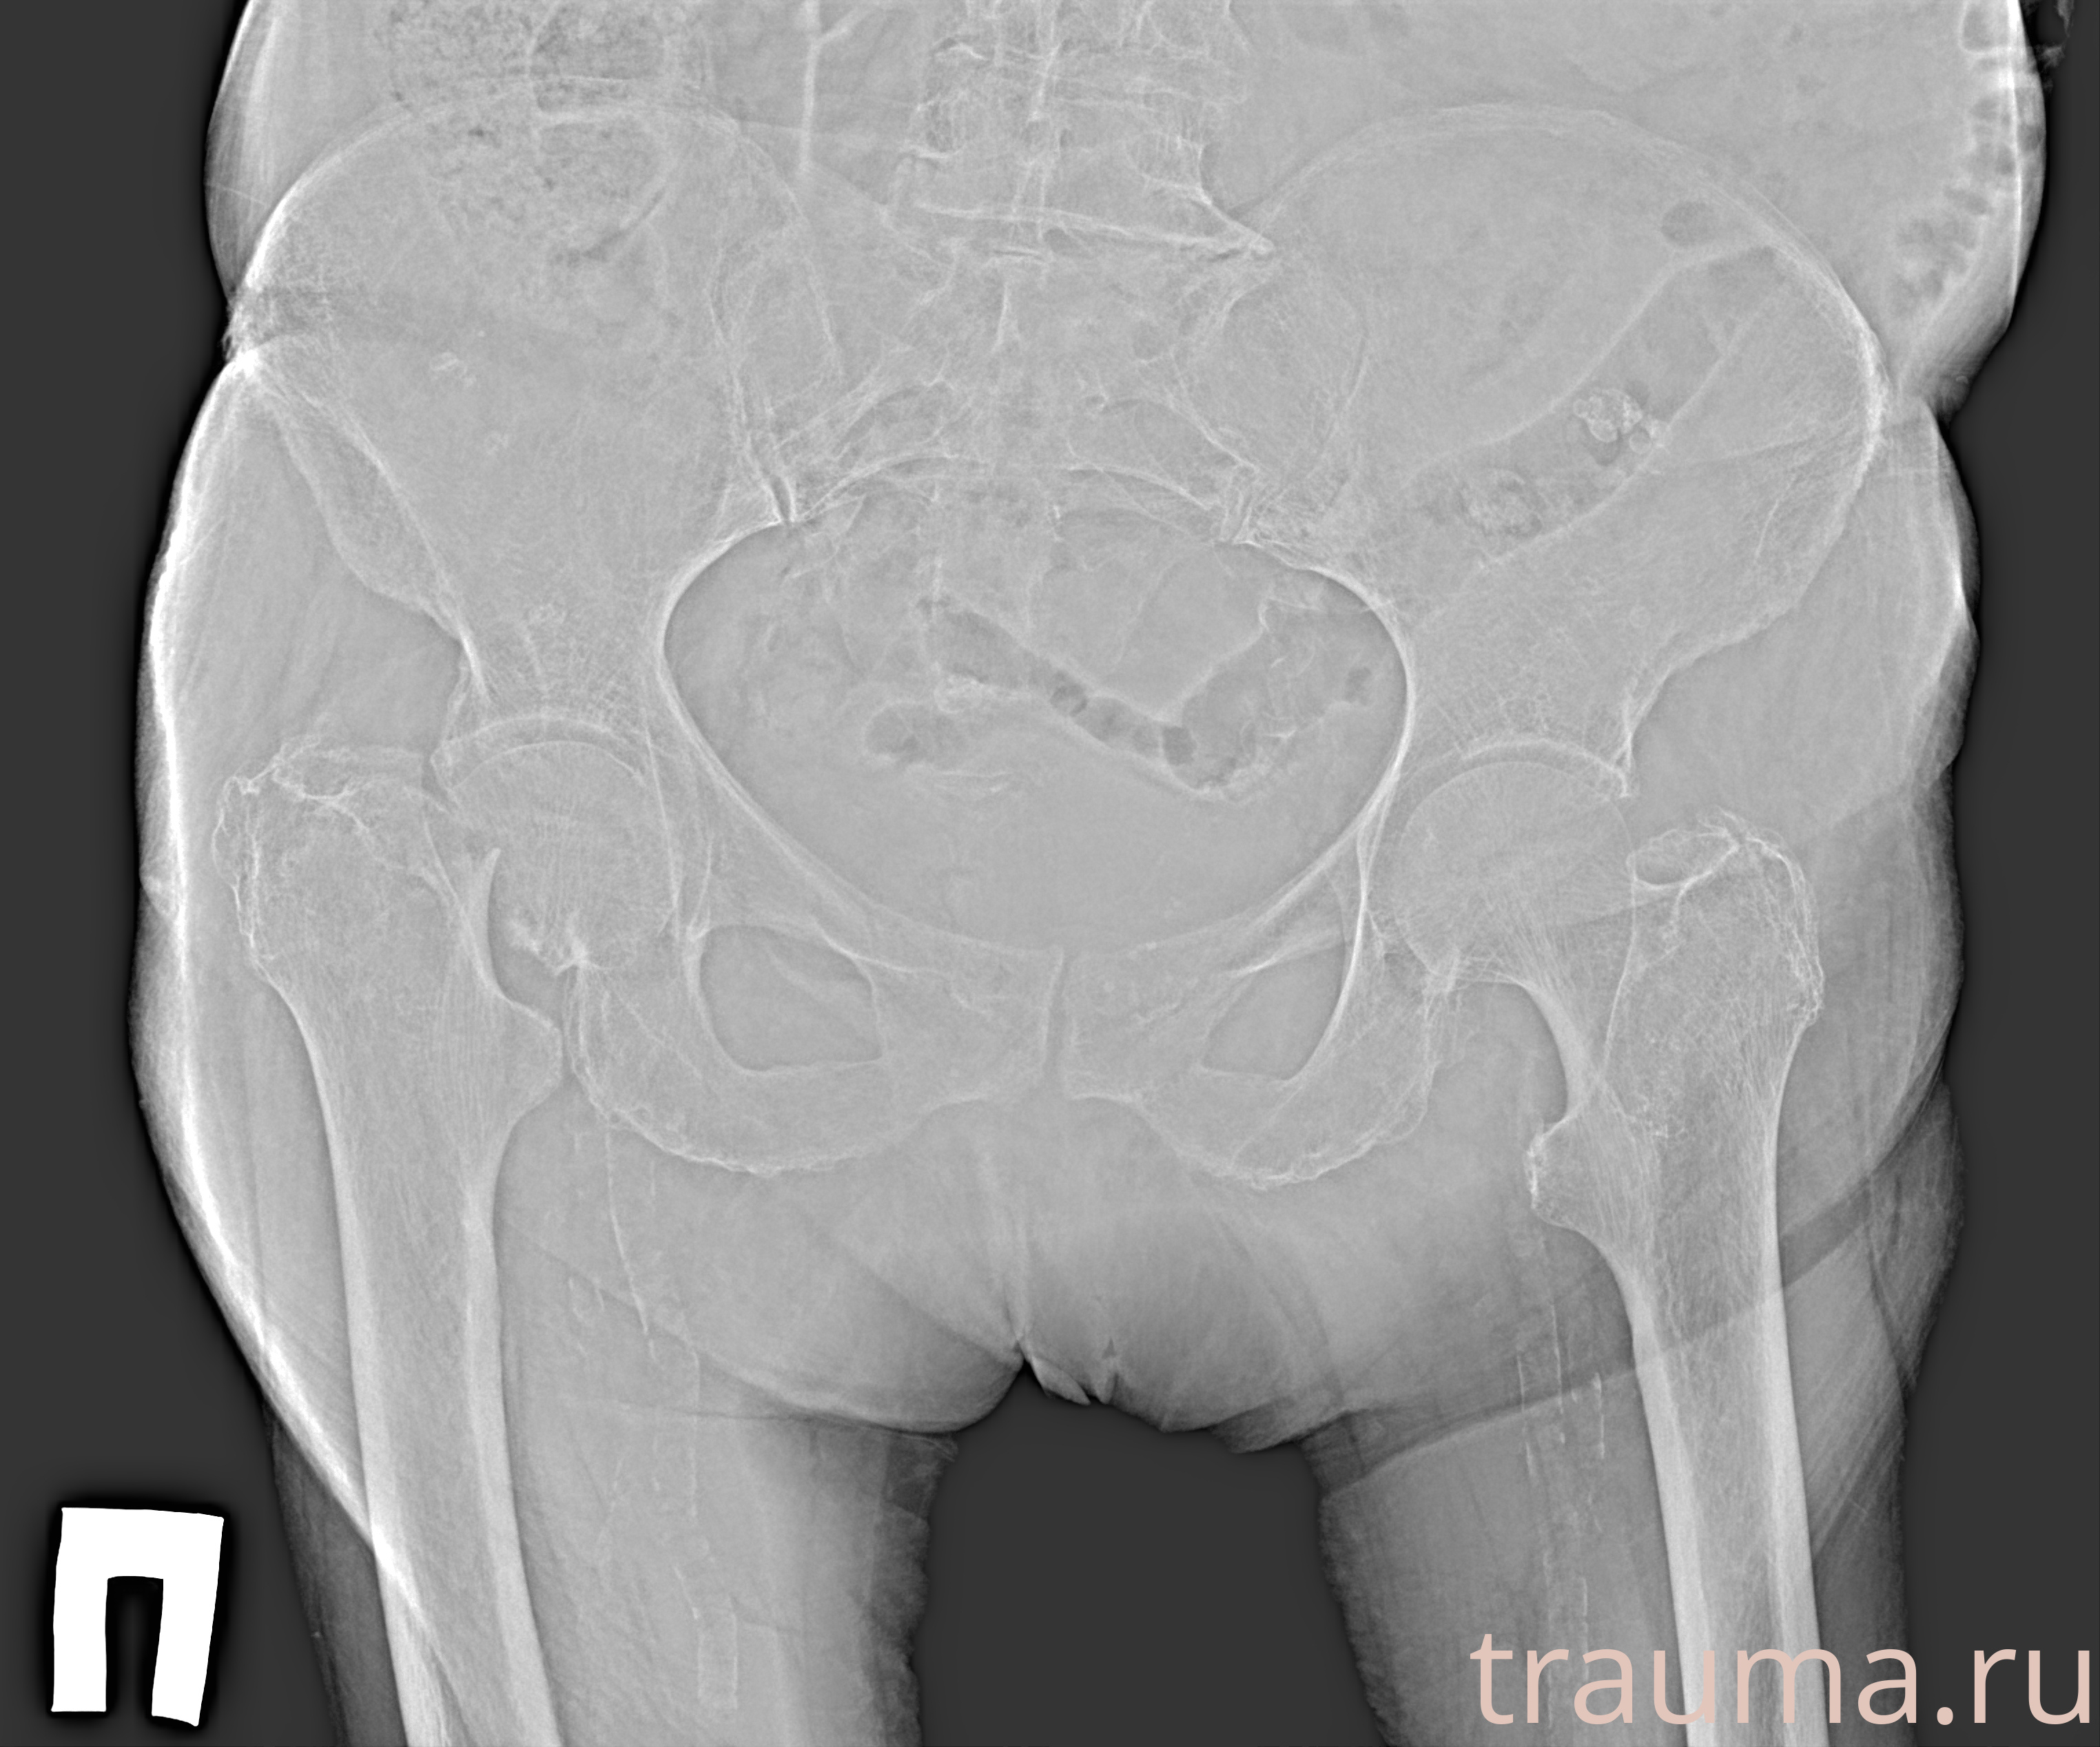

Рентген на дому: по вашему адресу приезжает врач-рентгенолог, травматолог-ортопед с мобильным рентгеновским аппаратом, проводит диагностику травмы или заболевания, делает необходимые рентгенограммы, дает рекомендации по дальнейшему лечению. Получить качественные снимки в домашних условиях возможно благодаря уникальной методике, разработанной МосРентген Центром для института  Склифосовского